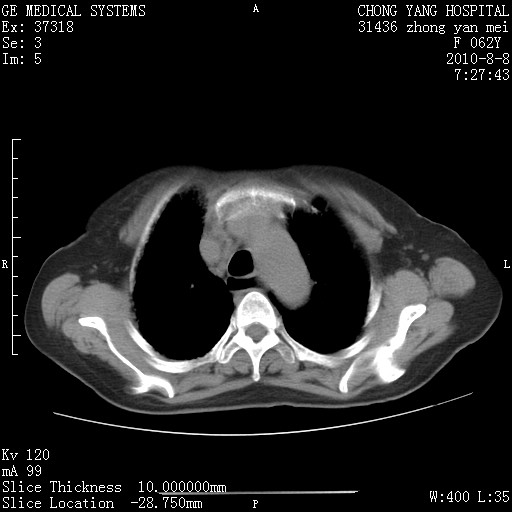

标题: CT28269:F62Y咳嗽胸痛数月。 [打印本页]

标题: CT28269:F62Y咳嗽胸痛数月。

两肺弥漫性间质纤维化伴继发性支扩。

考虑特发性肺间质纤维化

考虑两肺间质性肺炎并肺间质纤维化。

双肺间质纤维化合并感染、肺气肿

1.肺间质纤维化.

2.纵隔淋巴结肿大。

3.迷走右锁骨下动脉。

两肺间质改变,纵隔淋巴结肿大,需要考虑结节病的可能。